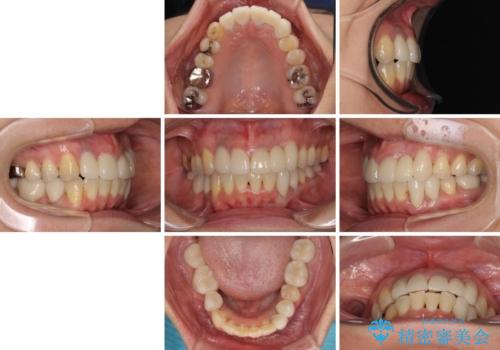

前歯の横幅が大きいことも気になっていたので、矯正治療で前歯5本の幅をコントロールしながら移動させ、治療開始前より一回りサイズの小さいセラミッククラウンを装着することができました。

矯正治療によって前歯にスペースを作り、左右対称となるようにオールセラミッククラウンにて補綴治療を行うとしました。

他にも奥歯の咬み合わせに問題があったので、全顎的な矯正治療を行い、前歯以外にも口を開けたときに目立つ奥の銀歯をセラミッククラウンにて補綴治療を行うこととしました。